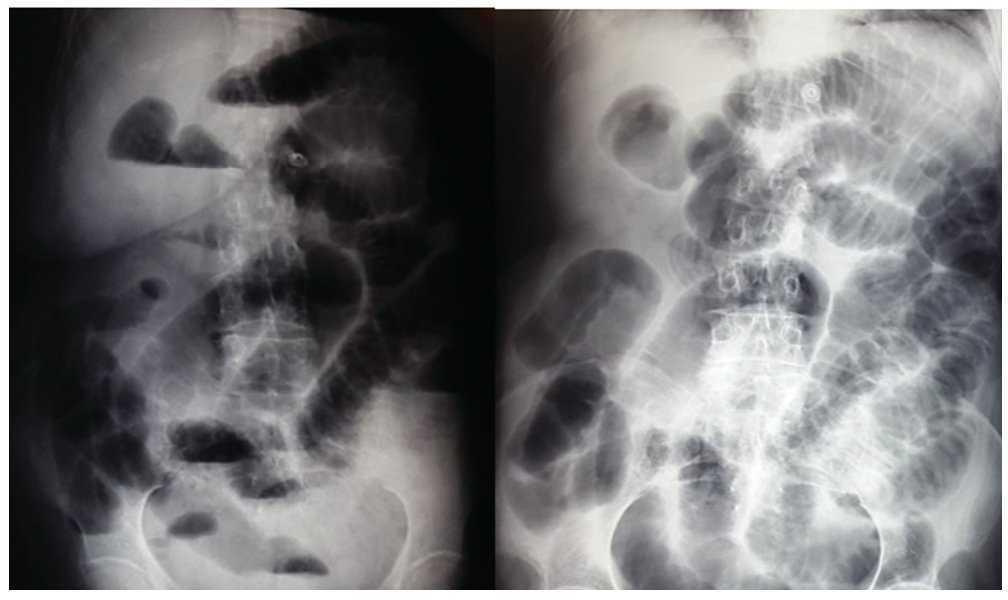

Se trata de paciente femenino de 77 años de edad, con antecedente de hipertensión arterial sistémica, ingresa a nuestro servicio por presentar cuadro doloroso abdominal intenso de una semana de evolución (fig. 1), acompañado de distensión abdominal náusea y vómito, el cual no remitió con la administración de analgésicos, acudió a valoración por facultativo quien solicitó ultrasonograma (USG) abdominal evidenciando la presencia de un tumor en colon derecho, se ingresó a la paciente por presentar persistencia de la sintomatología. A la exploración física hemodinámicamente estable se encontró abdomen distendido, doloroso a la palpación, superficial, media y profunda en cuadrantes abdominales inferiores y ruidos metálicos a la auscultación, con datos de irritación peritoneal. Paraclínicos con leucocitosis leve únicamente. En el USG abdominal reportó en flanco derecho una imagen ecogénica, redondeada, bien delimitada, con medidas de 41 x 38 x 59 mm en sus ejes mayores, la cual a la aplicación de Doppler color no mostró vascularidad, esta zona es aperistáltica, en relación a conglomerado de asas. No se identifica líquido libre. La TAC abdominal (fig. 2) con imágenes compatibles a oclusión intestinal probablemente secundaria a invaginación intestinal a nivel de ciego y colon ascendente, la cual condicionaba ascitis y neumatosis intestinal leve, además de probable adenoma suprarrenal derecho. Con lo anteriormente mencionado se infiere diagnóstico de invaginación intestinal, por lo cual se programa de urgencia para laparotomía exploradora.

Figura 1 Radiografía de abdomen de pie y decúbito al momento del ingreso de la paciente.